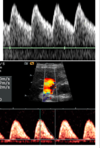

What pathology does this depict? [1]

Placenta praevia Fig 3 – Anterior placenta previa. The placenta (arrow) has covered the internal os completely (arrowhead).